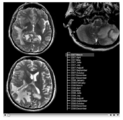

White matter lesion segmentation is now available as an extension to Slicer